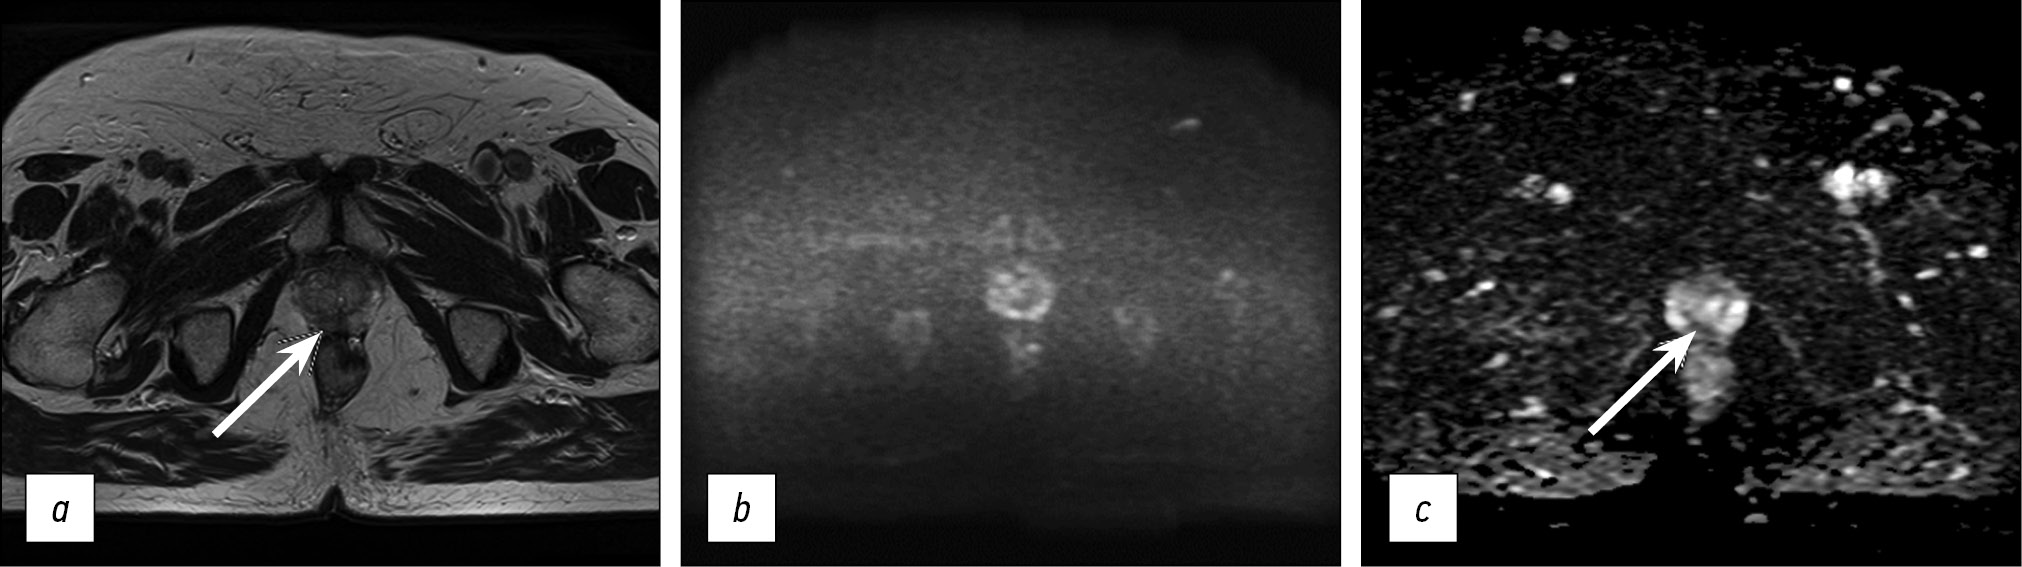

The resulting protocol provides a sufficiently high level of visualization quality. Fig. 5 presents images obtained using the optimized protocol. The total scanning time was less than 11 min.

Fig. 5. Images obtained using the accelerated protocol of biparametric magnetic resonance imaging. Patient with prostate changes consistent with PI-RADS 2: a) T2-WI, axial view; b, c) DWI and ICD.